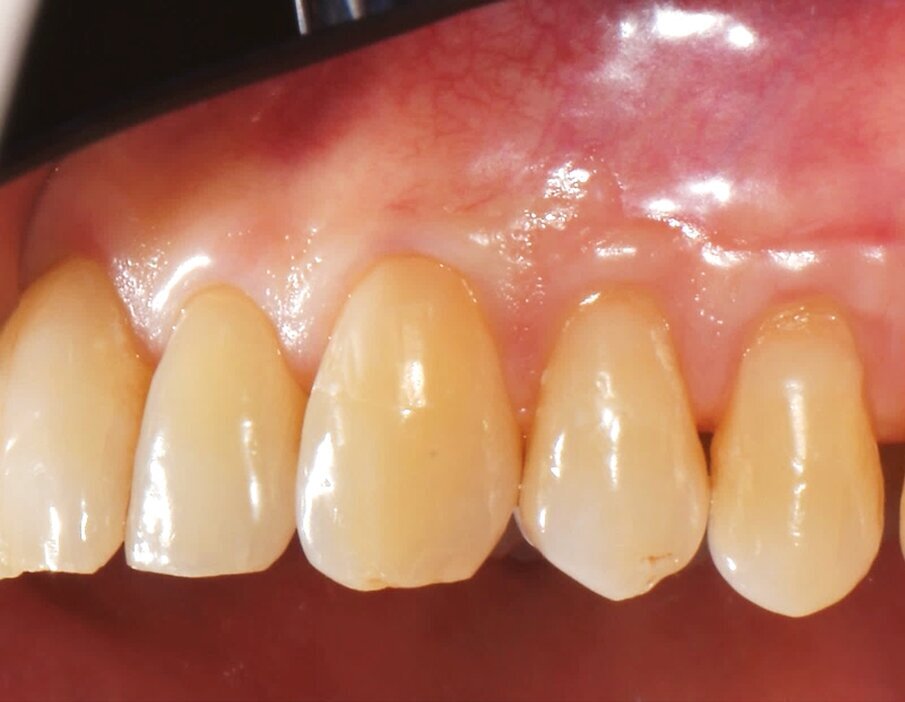

Le immagini dei controlli a 1 mese e ad 1 anno dimostravano come la tecnica MCAF con l’interposizione della matrice collagenica tridimensionale di origine equina (XC COLLAGEN Xenomatrix, Bioteck Spa) sia in grado di garantire un risultato stabile in termini di copertura radicolare (Figg. 7-10b).

Fig. 7 - Il controllo della guarigione a 1 mese evidenzia una buona integrazione dell’innesto e una maturazione ancora incompleta delle papille.

Fig. 8 - Controllo della guarigione a 1 anno: il sito trattato non presenta disarmonie cromatiche e di spessore in corrispondenza della mucosa orale.